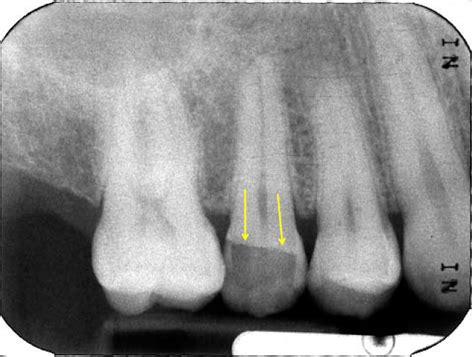

Remember that some icd 10 code for abscess tooth unspecified coupons only apply to selected items, so make sure all the items in your cart are eligible to be applied. International statistical classification of diseases and related health problems 10th revision. Most of these conventions, as we. S02.5xxa is a billable icd code used to specify a diagnosis of fracture of tooth (traumatic), initial encounter for closed fracture. Diseases of oral cavity and sinuses. Additional v, w, x, y codes. Fracture of tooth (traumatic), init for clos fx; The fracture description above is well defined and includes description that supports the necessary items such as traumatic, open, displaced, middle of femur shaft, subsequent encounter. Most ophthalmology codes are in chapter 7 (diseases of the eye and adnexa), but diabetic retinopathy codes are in. It is divided into chapters based on body part or condition. The 7th characters that can be added, and the resulting billable codes, are as follows The ahima cdi workgroup has responded to the needs • note: Remember that some icd 10 code for abscess tooth unspecified coupons only apply to selected items, so make sure all the items in your cart are eligible to be applied. Check out our list of faqs to make sure you're up to date on the. You may browse the classification by using the hierarchy on the left or by using the search functionality. Learn vocabulary, terms and more with flashcards, games and other study tools. 4 1 spondylosis with myelopathy, thoracic region 7 2 1.